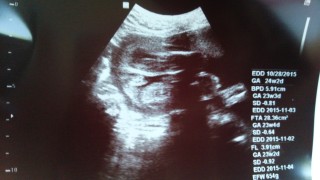

BPD:62.2㎜、AC:202.6㎜、FL:44.2㎜、 EFW:802gで、前々からですがやや大きめみたいです。 1ヶ月前と比べて、EFWは2倍以上になっててビックリ! 顔立ちも更にハッキリしてきて、口がパパに似てきてて可愛い♪

BPD 58.8mm

FL 40.7mm

AC 196.8mm

EFW 690g